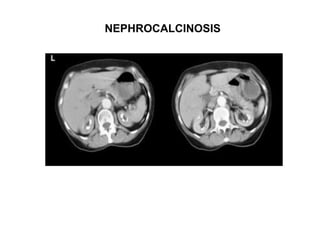

NEPHROCALCINOSIS